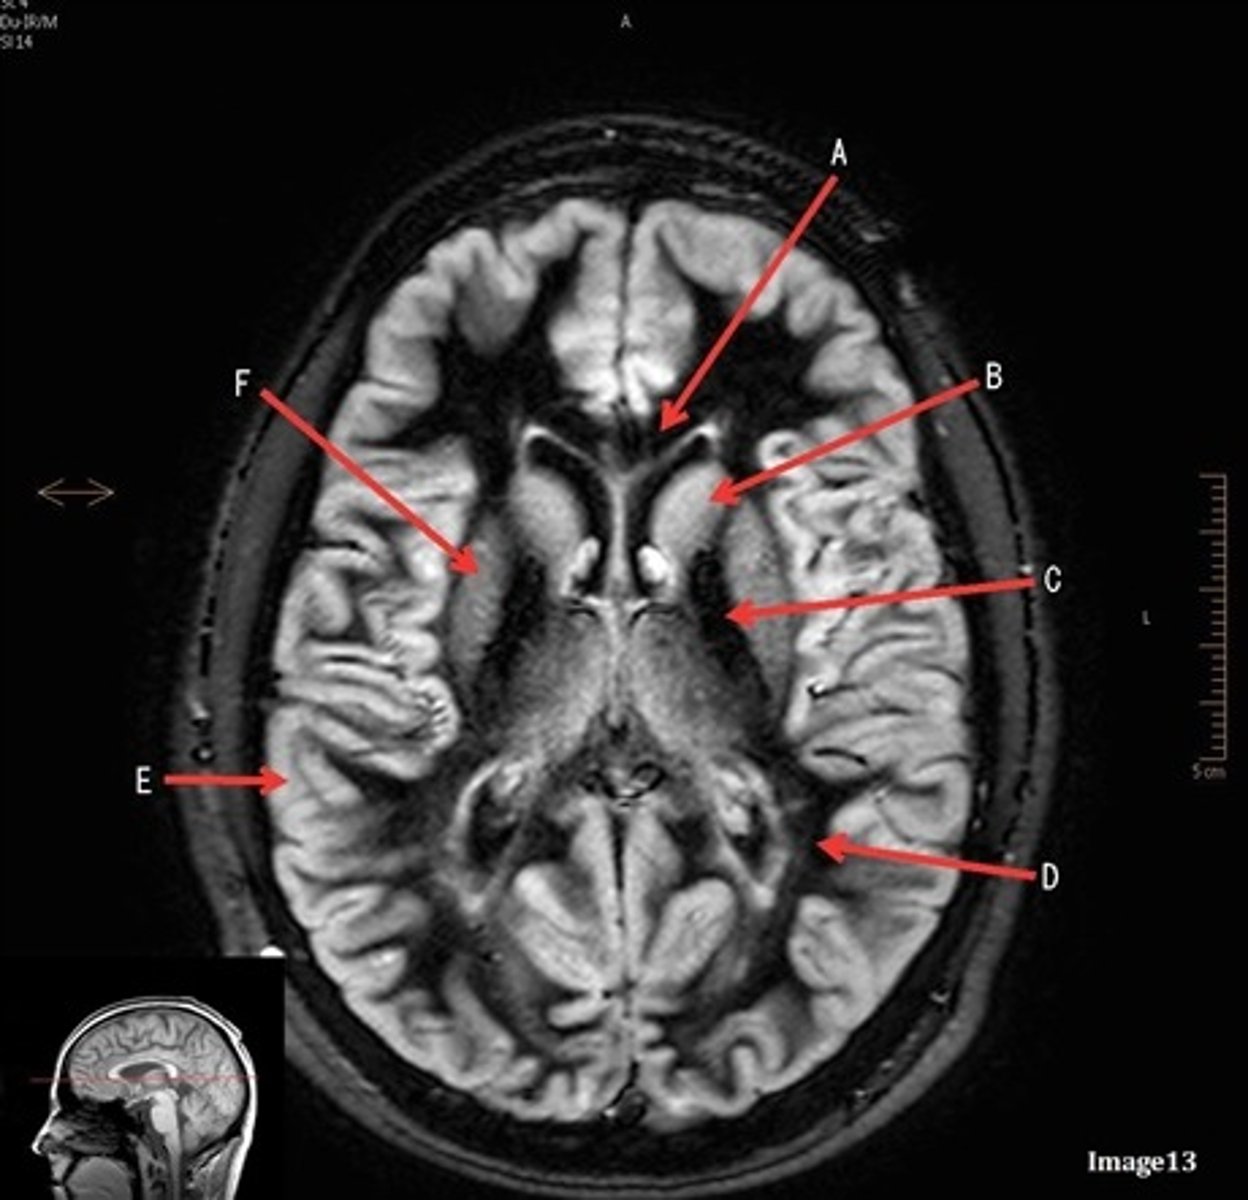

A

caudate nucleus

B

thalamus

C

third ventricle

D

lentiform nucleus

E

frontal sinus

A (region)

dark band is called?

basal ganglia region

internal capsule

posterior horn of lateral ventricle

anterior horn of lateral ventricle

white matter

F

gray matter

pituitary gland

lateral ventricle

corpus

fornix

internal carotid artery